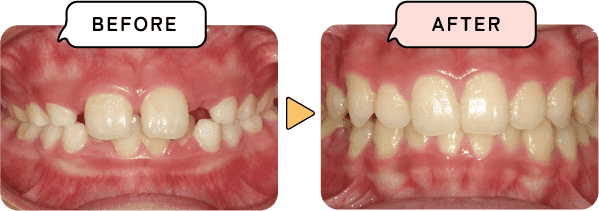

悪い歯並び・噛み合わせを何もしないで放置してしまうと不適切な状態で発育が進み、口の中だけでなく全身の発育や健康に悪影響を及ぼします。歯並びは子供一人一人に個性があります。矯正を必要とする歯並びもあれば、必要としない歯並びもあります。まずはお口の中を見せてください。そして不安なことを一緒に解決してきましょう。

歯が大きくなり、あごが小さくなることでスペースが足りず前後にデコボコした歯並びになります。

矯正の方法はたくさんありますが、当院では歯並びとからだ全体を健康にする「子ども顎顔面矯正」を中心にお子様の状態に合わせて、治療方法をご提案いたします。

お子様の成長発育に合わせて、本来あるべき正しい噛み合わせの状態を作ります。歯並びだけでなく、骨格矯正も含めた治療です。

骨格矯正をすることで、あごや顔・鼻腔の正常な発育をサポートします 。「歯並び」だけでなく「からだ全体」を健康にする矯正方法です。